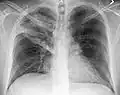

| A chest X-ray showing a very prominent wedge-shape bacterial pneumonia in the right lung | |

The discovery of x-rays made it possible to determine the anatomic type of pneumonia without direct examination of the lungs at autopsy and led to the development of a radiological classification. Early investigators distinguished between typical lobar pneumonia and atypical (e.g. Chlamydophila) or viral pneumonia using the location, distribution, and appearance of the opacities they saw on chest x-rays. Certain x-ray findings can be used to help predict the course of illness, although it is not possible to clearly determine the microbiologic cause of a pneumonia with x-rays alone.